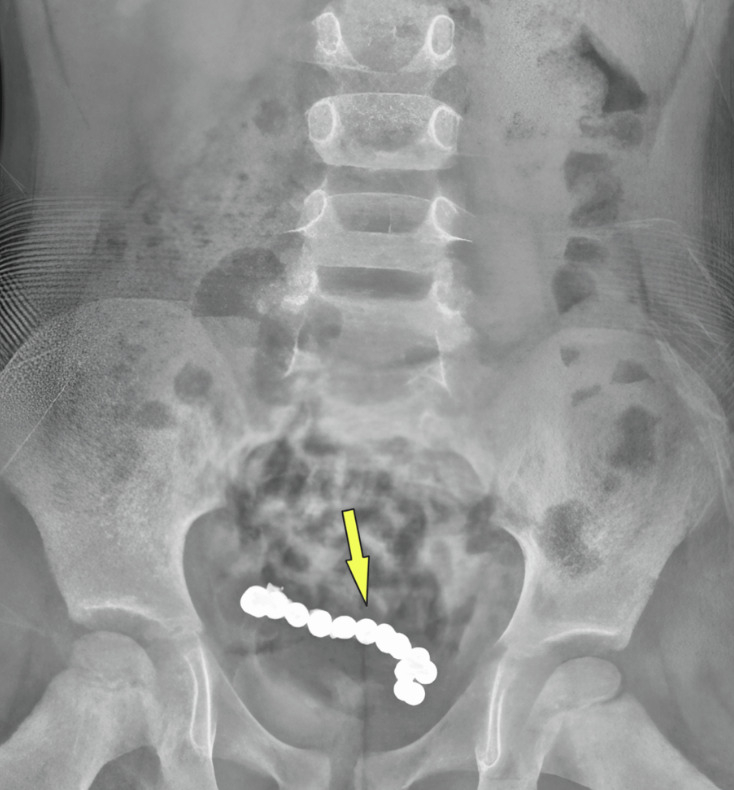

그러나 상태는 호전되지 않았고, 이후 재촬영한 복부 CT에서 아이의 하복부에 둥근 이물질 여러 개가 사슬처럼 연결돼 있는 것이 관찰됐다. 이물질의 정체는 자석으로 확인됐으며 아이가 1년 전 자석을 섭취했지만 배출되지 못한 것으로 추정된다.

자석으로 인해 장 일부가 괴사돼 아이는 장의 약 15㎝를 절제했다. 수술을 마친 아이는 4일 만에 안정된 상태로 퇴원했고, 3개월 뒤 받은 검진에서도 특별한 이상 소견이 발견되지 않았다.